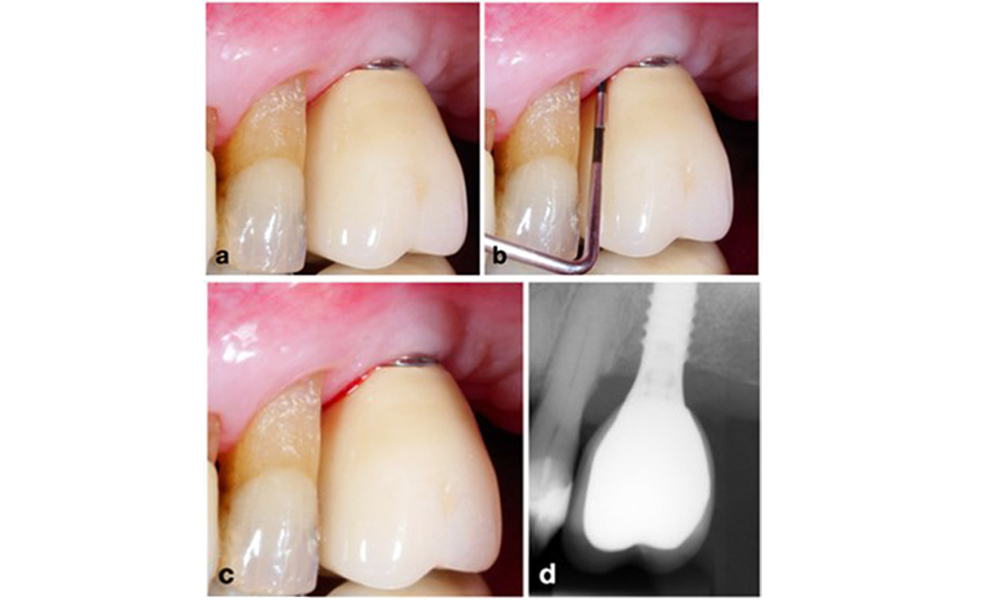

La péri-implantite est identifiée par (1) des signes d'inflammation similaires à la mucosite, (2) des preuves radiographiques de perte osseuse après la cicatrisation initiale et (3) une augmentation de la profondeur de sondage par rapport aux mesures prises peu après la mise en place de la reconstruction prothétique (figure 2). En l'absence de radiographies antérieures, un niveau osseux radiographique de ≥ 3 mm, accompagné d'un saignement au sondage et d'une profondeur de sondage ≥ 6 mm, indique une péri-implantite.

Restauration de l'arcade complète avec péri-implantite à des degrés divers sur certains implants. L'implant en position 21 est sévèrement atteint avec des profondeurs de sondage allant jusqu'à 9 mm (a), un saignement au sondage, une suppuration du sillon péri-implantaire et une fistule vestibulaire (b-c) ; la radiographie montre une perte osseuse d'environ 50 % pour l'implant atteint de péri-implantite en position 21, tandis que l'implant en position 23 présente une perte osseuse limitée, correspondant approximativement à ce que l'on peut attendre après la cicatrisation initiale pour ce type d'implants (d).

Figure 2. Restauration de l'arcade complète avec péri-implantite à des degrés divers sur certains implants. L'implant en position 21 est sévèrement atteint avec des profondeurs de sondage allant jusqu'à 9 mm (a), un saignement au sondage, une suppuration du sillon péri-implantaire et une fistule vestibulaire (b-c) ; la radiographie montre une perte osseuse d'environ 50 % pour l'implant atteint de péri-implantite en position 21, tandis que l'implant en position 23 présente une perte osseuse limitée, correspondant approximativement à ce que l'on peut attendre après la cicatrisation initiale pour ce type d'implants (d).

La perte osseuse attendue après la cicatrisation initiale, attribuée au remodelage de l'os marginal, varie en fonction de facteurs tels que le système ou le type d'implant. Par exemple, une perte osseuse de 1 à 2 mm est généralement considérée comme "normale" pour les implants au niveau de l'os avec une connexion externe (figure 2d, implant en position 23).